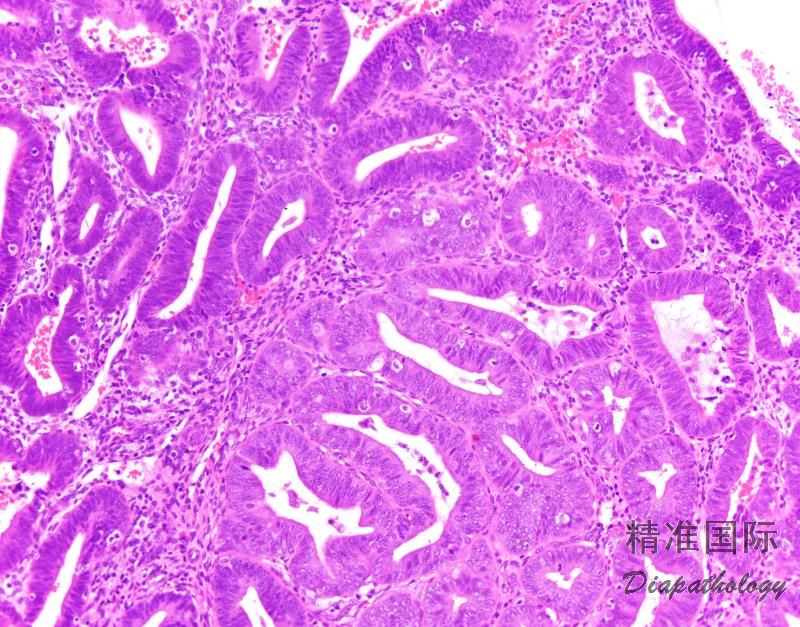

表现为细胞复层化、极性消失,细胞核增大及核/质比增加,核分裂像多少不等;

细胞核趋于圆形,核透亮或空泡状,染色质粗糙、块状,染色质凝缩边集于核膜周围,核膜增厚、不规则,核仁明显;

复杂性非典型增生的腺体结构是高度复杂、形状不规则,并有“背靠背"密集现象。